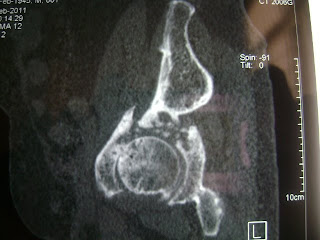

32 year old financially challenged girl with painful hip. She has a foot drop . grade 4+ hip abductors and flexors

problems1. dyspalstic acetabulum

coxa calga

narrow osteoporotic femoral canal.